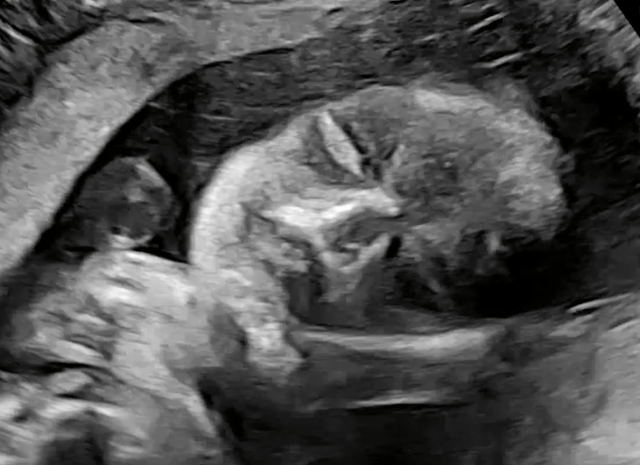

아들놈인데 얼굴은 다행히도 와이프 닮은거 같고

입벌리고 쳐자는건(?) 저를 닮았네요..